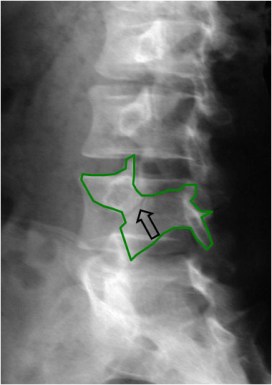

Signo de espondilolisis en la radiografía oblicua de columna lumbar. La imagen del perrito, un hallazgo clásico en radiología, está formada por: la apófisis transversa (la nariz), el pedículo (el ojo), la pars interarticularis (el cuello), la apófisis articular superior (la oreja) y la apófisis articular inferior (la pataa delantera).

El collar del perrito es la línea radiolucente (flecha) por rotura de la pars interarticularis.